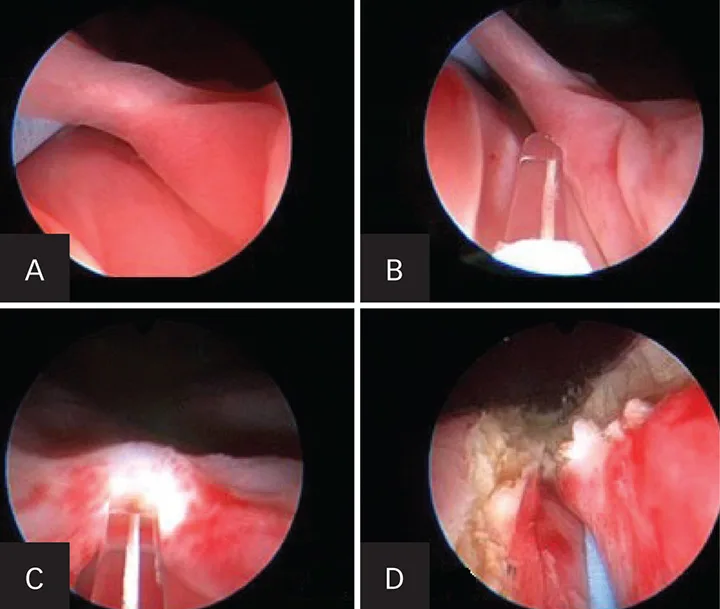

In dogs, ectopic ureters are a common congenital anatomic deformity. The ureteral orifice is positioned distal to the bladder trigone within the uterus, vestibule, or vagina. More than 95% of ectopic ureters in affected dogs transverse intramurally and are candidates for the procedure. A laser is used to cut the intramural ectopic tunnel in this endoscopic procedure (Figure 4).

Figure 4. Endoscopic images during cystoscopic-guided laser ablation in a female dog with an intramural ectopic ureter. Guide wire in the ureteral lumen caudal to the trigone of the bladder (A). Laser fiber through the working channel of the endoscope before laser ablation (B). Laser fiber cutting the medial ureteral wall within the urethral lumen (C). The neoureteral orifice after cystoscopic-guided laser ablation (D).

In the author’s practice, more than 80 dogs (male and female) have successfully undergone endoscopic repair of ectopic ureters. This procedure is performed in conjunction with cystoscopy, fluoroscopy, and a diode or holmium: yttrium-aluminum-garnet (YAG) laser. This outpatient procedure is completed at the time of cystoscopic diagnosis of ectopic ureter, reducing the number of anesthesia events. A recent prospective study in the veterinary literature has shown promising results.3